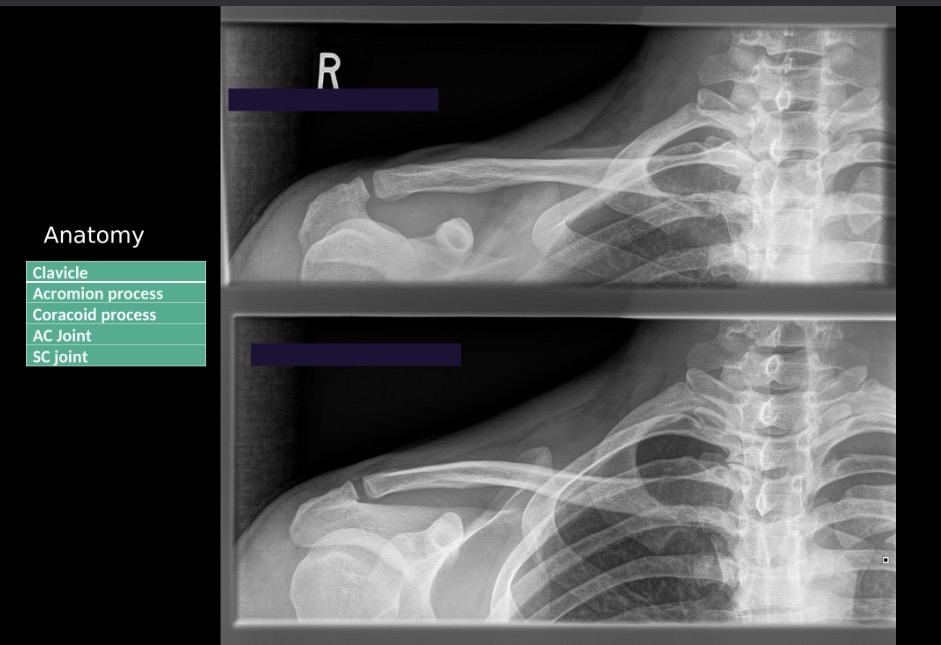

What Projection Position is the Top Photo?

AP Axial Clavicle

What projection position is the bottom image?

AP Clavicle